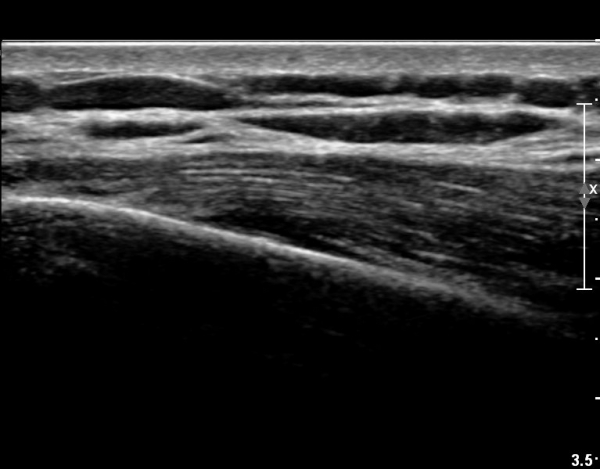

8¹øÂ° °¥ºñ»À ¾ÕÂÊ  Á¾´Ü¸é°Ë»ç»ó  Æ¯ÀÌ ¼Ò°ßÀ» º¸ÀÌÁö ¾ÊÀ¸¸¶(»çÁø 4)

ŽÃËÀÚ¸¦ µÚÂÊÀ¸·Î À̵¿ ÇÏ´Ï °¥ºñ»À Ç¥ÃþÀ¸·Î Àú¿¡ÄÚ ºÎÁ¾ÀÌ °üÂûµÈ´Ù(»çÁø 3).